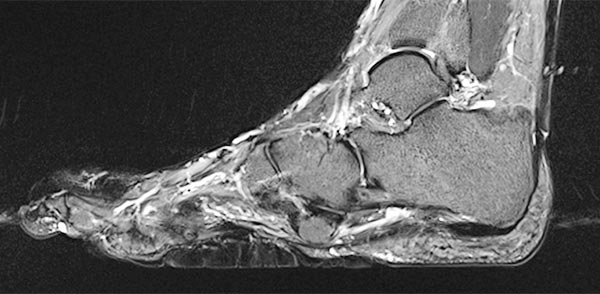

Preoperative imaging of the cerebriform mixed connective tissue nevus in MRI, here sagittal T2-weighted, fat-suppressed sequence of the right foot. The connective tissue nevus is homogeneously hypointense (black) due to the high fibrotic content.

The cerebriform mixed connective tissue nevus is also homogeneously hypointense (black) on sagittal non-enhanced, T1-weighted MRI (same plane).

Sagittal , T1-weighted, fat-suppressed MRI (again, the same plane) shows slight, relatively homogeneous contrast enhancement of the nevus.